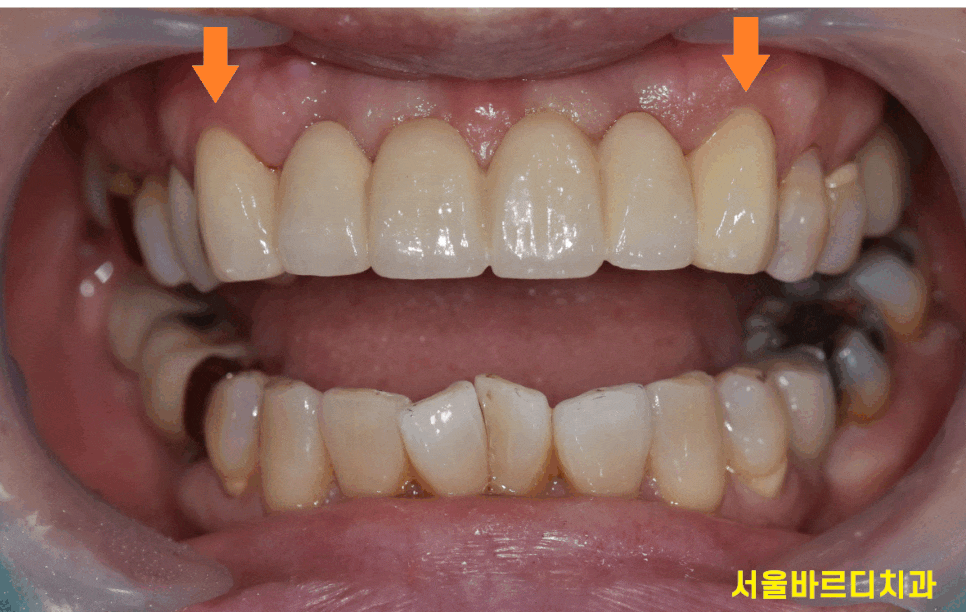

앞니 보철이 깨졌네요~

깨진 것도 그렇지만

앞니 잇몸 검은색 라인 까매서 보기 싫다고 하셨는데요.

약간 잇몸이 거뭇거뭇하게 보이는걸

보실 수 있으실텐데요~

충치는 아니고 pfm 보철로 하셔서

저렇게 보이는겁니다!